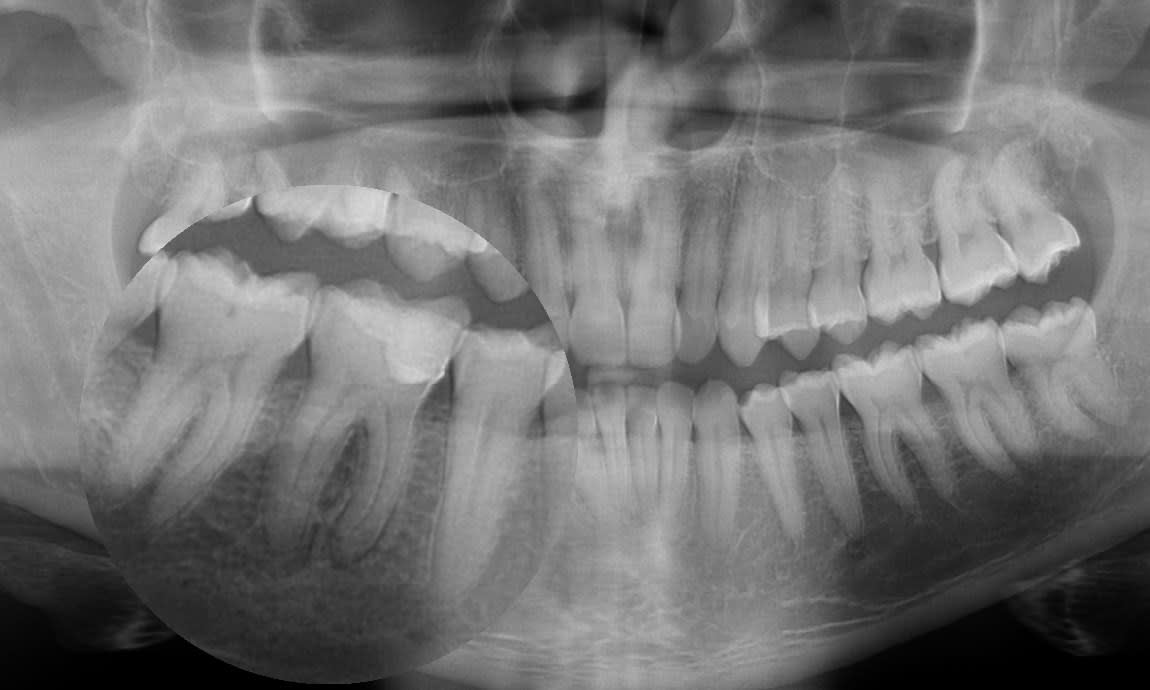

Utilisateur banni

13/01/2017 à 17h48

Couronnes provisoires jumelées exprès pour vous sur dents divergentes 😊

Je tiens à préciser pour les vieilles branches vicieuses qu'en postérieur y a pas de PPA car j'ai posé des Implants

Img 0664 akswpo - Eugenol

Img 0661 wbeclb - Eugenol

Img 0663 bpgzq4 - Eugenol